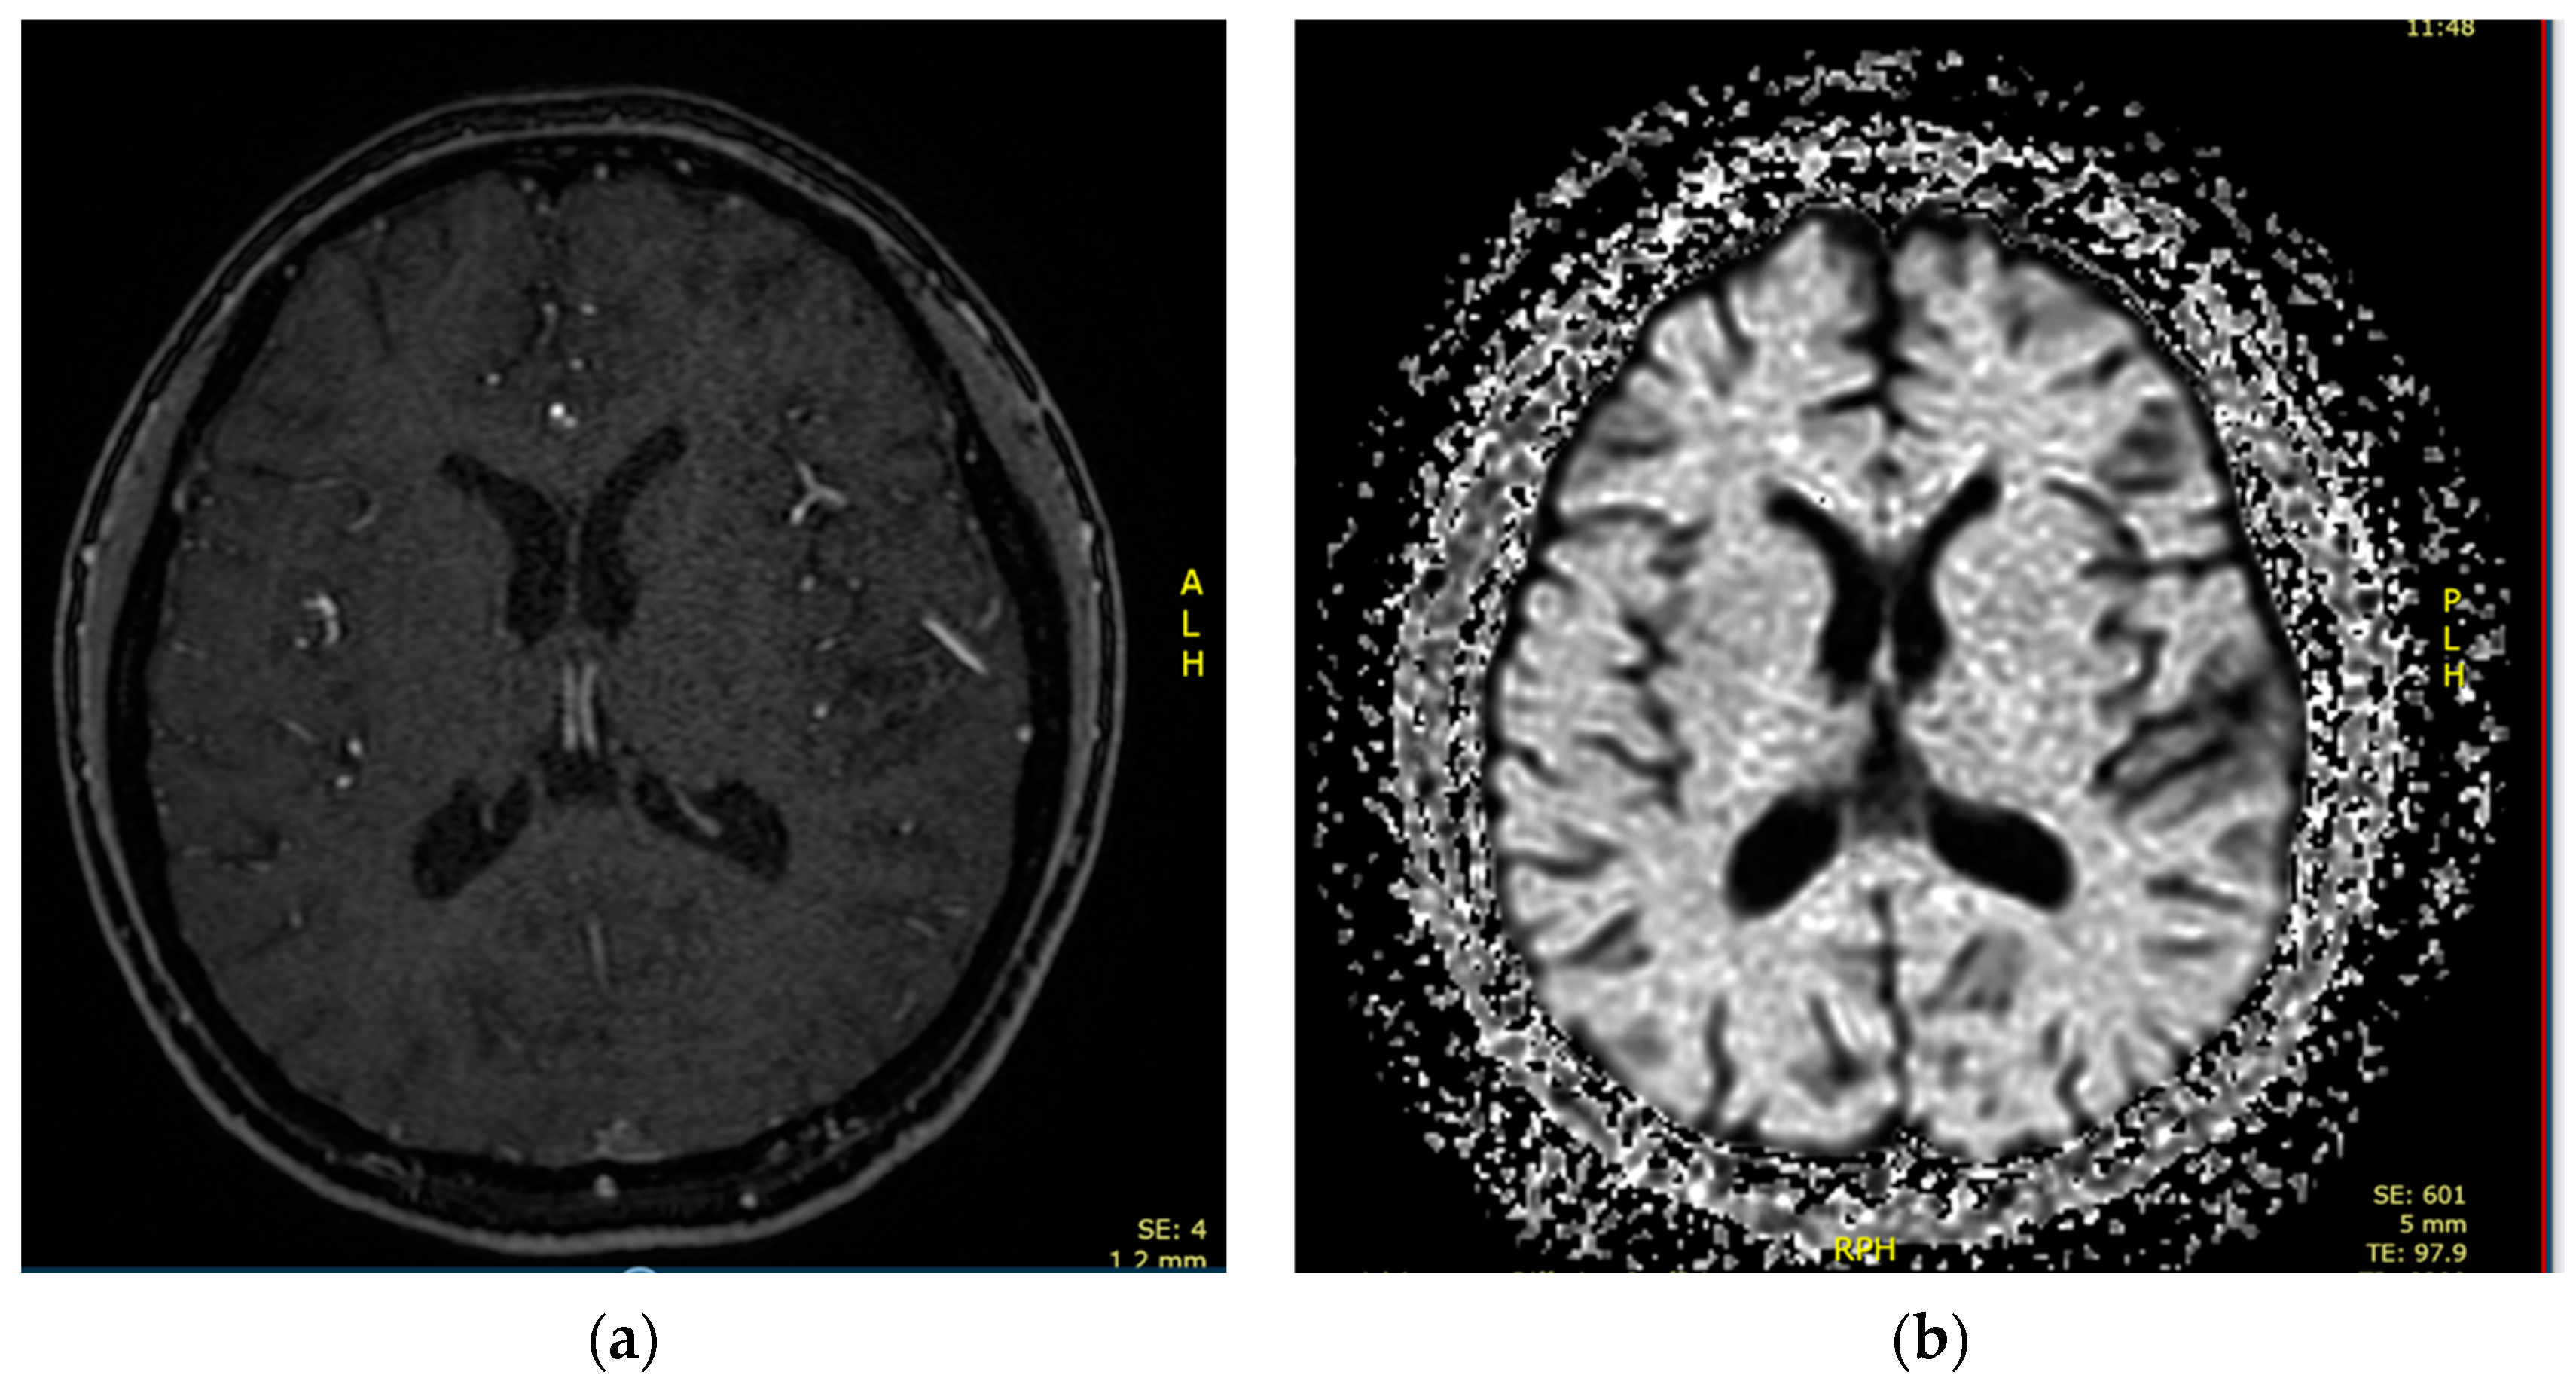

2.1. Case 1

2.2. Case 2

2.3. Case 3